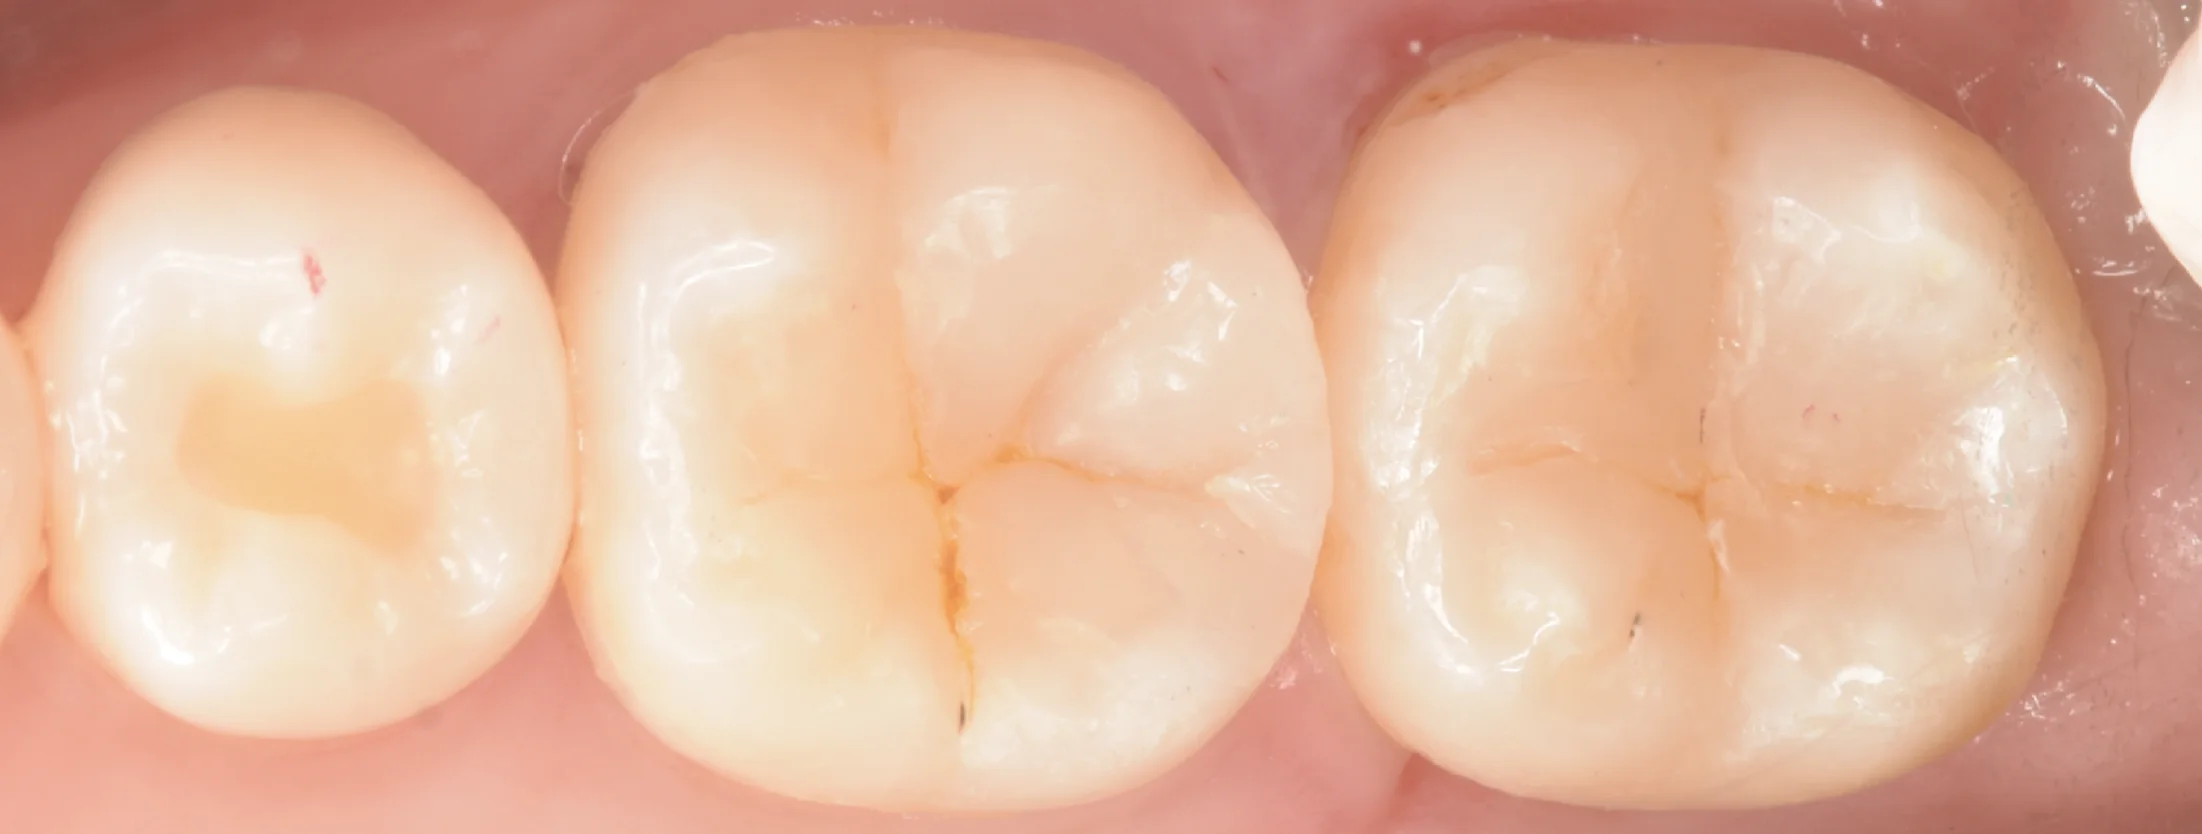

さて、古い詰め物を除去したのがこちらになります。

旧修復物除去時

広範囲にうっすらと虫歯になってしまっています。

歯の境目には全くむし歯はなく、内部にむし歯があるので、右については取り残しと考えられます。

左側のむし歯については境目あたりにもむし歯があるため、接着不良が一番怪しいです。